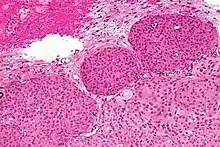

Los meningiomas presentan un amplio espectro de fenotipos histopatológicos. Los más frecuentes son el transicional, el meningotelial y el fibromatoso. Se describen a continuación los subtipos histopatológicos mejor caracterizados.[4][2][7]

Meningioma meningotelial

Se caracteriza por su microarquitectura lobular y apariencia epiteliode. La neoplasia está poblada de células que tienen núcleos, redondos u ovales, de cromatina delicada y nucleolos poco llamativos. Los citoplasmas son eosinófilos, claros, y el borde citoplasmático indistinguible, de ahí su designación alternativa como meningioma sincitial. Es común, al igual que en otros subtipos, que las células tumorales se agrupen en apretadas espirales. También son frecuentes los núcleos claros, las pseudoinclusiones nucleares pálidas, resultantes de invaginaciones intranucleares del citoplasma, y la presencia de calcoesférulas laminadas, denominadas cuerpos de psammoma. Los hallazgos descritos son considerados como clásicos de los meningiomas y, aunque ninguno de ellos es patognomónico, su demostración tiene un considerable peso diagnóstico.